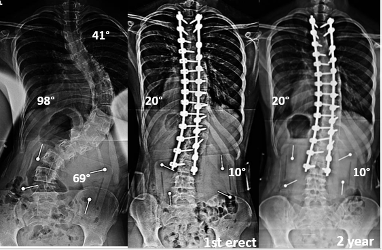

بعض الأطباء ينصحون بالجراحة عند تجاوز زاوية الانحناء 45 إلى 50 درجة، ظنًا أن الجراحة الحل الأمثل لتقويم العمود الفقري بسرعة. لكن الجراحة ليست دائمًا الخيار الأفضل، فهي تحمل مخاطر ومضاعفات، وقد تؤثر على مرونة العمود الفقري لاحقًا.

تُعرف باسم “دمج الفقرات” أو Spinal Fusion، حيث يتم تثبيت فقرات العمود الفقري باستخدام قضبان ومسامير لمنع الانحناء من التزايد. رغم فعاليتها في السيطرة على الانحناء، إلا أنها لا تعيد العمود الفقري إلى استقامته الكاملة دائمًا. التعافي من الجراحة قد يستغرق أشهرًا، ويُفقد المريض جزءًا من مرونة الظهر، ما قد يقيّد الأنشطة اليومية لاحقًا.

حتى بعد الجراحة، قد يبقى هناك انحناء بسيط، وبعض المرضى يعانون من تيبّس أو آلام مزمنة. في بعض الحالات، قد يحتاج المريض إلى جراحة تصحيحية مستقبلية. لهذا، يوصي الخبراء عالميًا بمحاولة العلاجات غير الجراحية أولًا، خصوصًا في حالات الجنف مجهول السبب عند المراهقين.

العلاج غير الجراحي يتطلب التزامًا من الأهل والمريض ومراقبة دقيقة للانحناء باستخدام الأشعة وتحليل زاوية “كوب” (Cobb Angle). هذه المتابعة تضمن تعديل خطة العلاج بما يتناسب مع تطور الحالة.

متى تكون الجراحة ضروريه لعلاج اعوجاج العمود الفقري؟

الجراحة خيار أخير فقط في الحالات التالية:

فشل جميع العلاجات غير الجراحية.

تزايد الانحناء بسرعة رغم الالتزام بالعلاج.

ظهور أعراض عصبية أو ألم شديد لا يُحتمل.

تابعوا قياسات زاوية “كوب” لضمان فعالية العلاج.